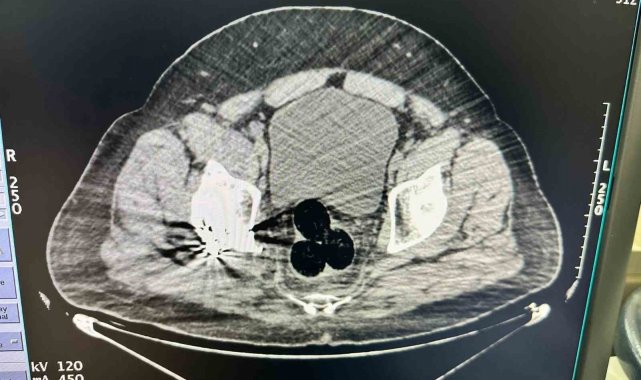

Edinilen bilgiye göre, İl Emniyet Müdürlüğü Narkotik Suçlarla Mücadele Şube Müdürlüğü ekipleri, İran'dan Türkiye'ye yasa dışı yollardan giriş yapan bir kişiyi şüphe üzerine takibe alındı. Gözaltına alınan şahıs hastaneye götürüldü. Hastanede yapılan görüntülemede şüphelinin makat bölgesinde üç parça halinde yabancı cisim tespit edildi. Cerrahi müdahale ile çıkarılan paketlerde toplam 130 gram metamfetamin ele geçirildi, şüpheli gözaltına alındı. Soruşturmayı derinleştiren polis ekipleri, uyuşturucunun kentte dağıtımını yaptığı değerlendirilen iki şüpheliyi daha yakaladı. Bu kişilerin üzerinde ve adreslerinde yapılan aramalarda 47 gram daha metamfetamin ele geçirildi.

Iğdır'da, İran'dan Türkiye'ye yasa dışı yollardan giriş yapan şahsın radyolojik muayenesinde makatında uyuşturucu madde tespit edildi. Şüpheli ile bağlantılı olduğu belirlenen 2 kişi, çıkarıldıkları mahkemece tutuklandı.